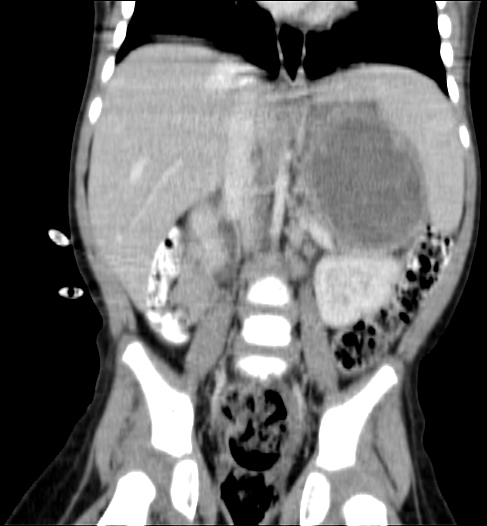

Papa collected copy of CT (CAT) scan images from Radiology. Looking at them it seems that the main tumour shrank from around 11 cm to 6 cm and there is less evidence of Nodes. But we have to await Radiology Report to be sure about this positive news. Lets hope Papa is right.

Today we got the Radiology Report back of the 25 August CT (CAT) scan. Papa still has a few remaining questions about it but it confirmed that the tumour shrank as papa thought to see himself from the images. Good news!